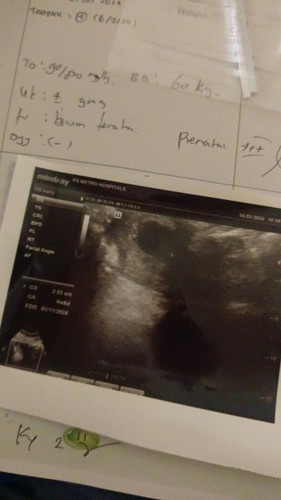

Bun aku usg pas 6 w 6 hari baru keliatan kantongny. Dan dsruh balik 2 mnggu lg. Itu wajar atau tdk g

Usg 6 minggu6 hari